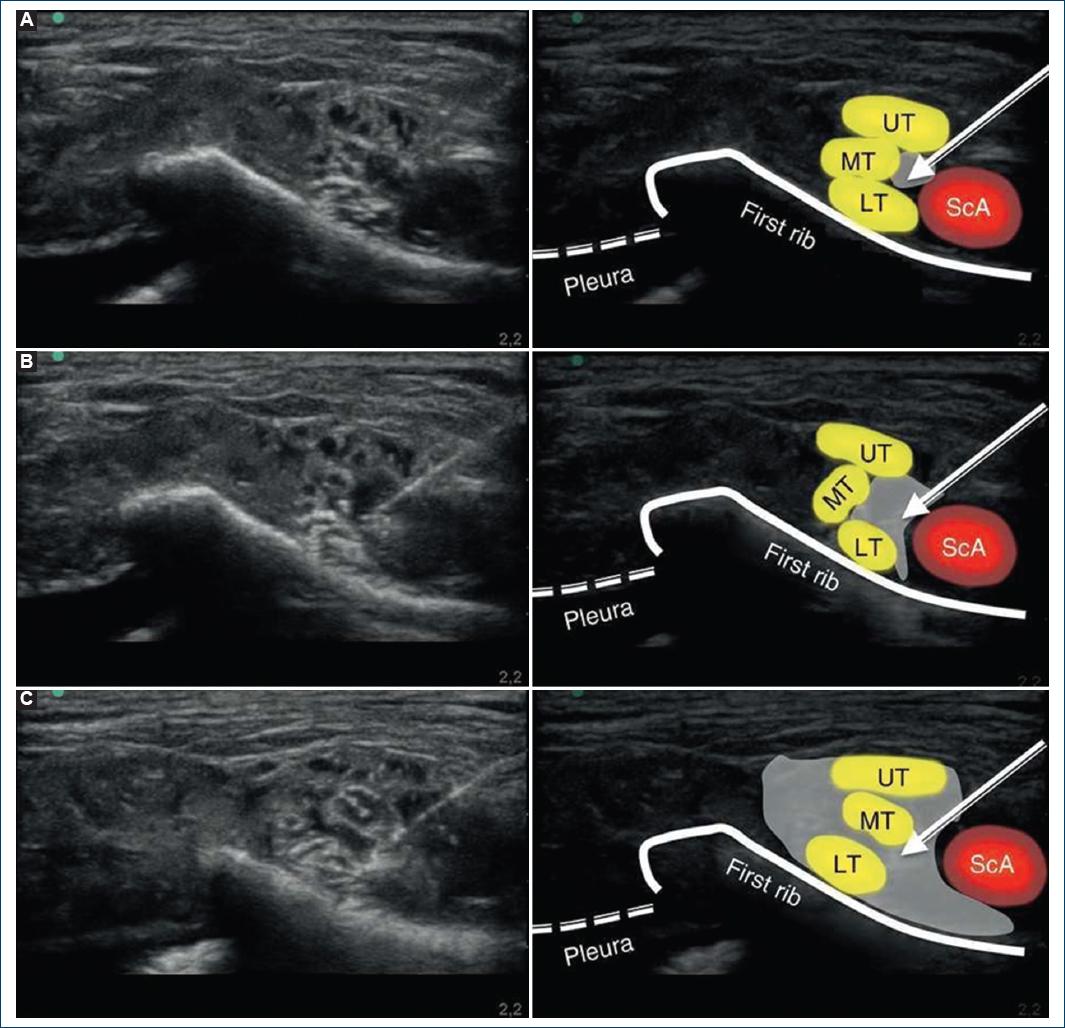

Although rare, RLN palsy has been documented in 1.3% of cases of classical SCB13. It has mostly been reported in the right-sided block which is well explained by its relationship with the right subclavian artery (SCA). The right and left RLNs follow different courses14 (Fig. 1). The right RLN encircles the right SCA and is in its close proximity. Hence, there are chances of its involvement in rare cases when a large amount of LA is deposited near the artery where the RLN is located. Hence, when the drug is deposited near SCA, there remains the possibility of involvement of RLN due to close proximity of the neurovascular structure, and more so when a large volume of the drug has been deposited15. However, the left RLN is much medial in relation to the left SCA running closer to trachea and esophagus. It is the left vagus nerve which runs near the SCA. The mechanism by which the nerve block occurred in our case was the exclusive block of the fibers of RLN present in the vagus nerve or unilateral vagus nerve as the drug deposited moved medial to the SCA and since the RLN is located farther. Visualization of the tip of the needle throughout the procedure is of utmost importance as this prevents the puncture of unwanted structures preventing complications and increases the chances of success of the procedure by deposition of LA at exact location16-18 (Fig. 2). The fascial sheath surrounding the brachial plexus is a determinant for the spread of LA. The sheath is a derivative of the deep cervical fascia and terminates by merging with the medial intermuscular septum of the arm. The LA injected spreads up and down the nerves in a longitudinal manner and circumferential spread are limited by the fascial sheath. When the large volume of LA is injected, there is a possibility of proximal spread of excessive drug involving RLN and attributing the hoarseness of voice19. As it happened with our patient the volume of the drug used might have been an additional contributing factor for the excessive spread. There is a remote possibility of aberrant left RLN (incident 0.04%) when it is known as non-recurrent inferior laryngeal nerve, it runs closer to the SCA and is always associated with aberrant vessels such as arteria lusoria, right aortic arch, and situs inversus20. Cases have been reported of respiratory obstruction as a result of unilateral SCB plexus block. In our case, it was self-limited; it only caused a feeling of discomfort in the patient. For similar reason, interscalene brachial plexus block should be avoided21,22. Various techniques have been described to limit the spread of injected LA into the brachial plexus23. These include the use of tourniquet position of the arm, use of massage of the area for around 5-10 min, multiple injection techniques, digital pressure proven by Gupta et al.8, and elevated the head end of the bed by 30°. Based on the radiological evidence, digital pressure has been touted as an effective method to halt progression of LA into areas of the brachial or cervical plexus during brachial plexus block24.

Figure 2 Ultrasound image captured during the administration of the supraclavicular block using a medial approach on the anatomic specimen. A: position of the needle at the injection site. B: ultrasound image during the 10 ml injection. C: ultrasound image after completing the 20 ml injection. ScA: subclavian artery; UT: upper trunk; MT: middle trunk; LT: lower trunk. The arrow points toward the position of the neurostimulation needle. The gray shade shows the distribution of the volume injected at the injection site evaluated with ultrasound. From Herrera AE. et al 201710.